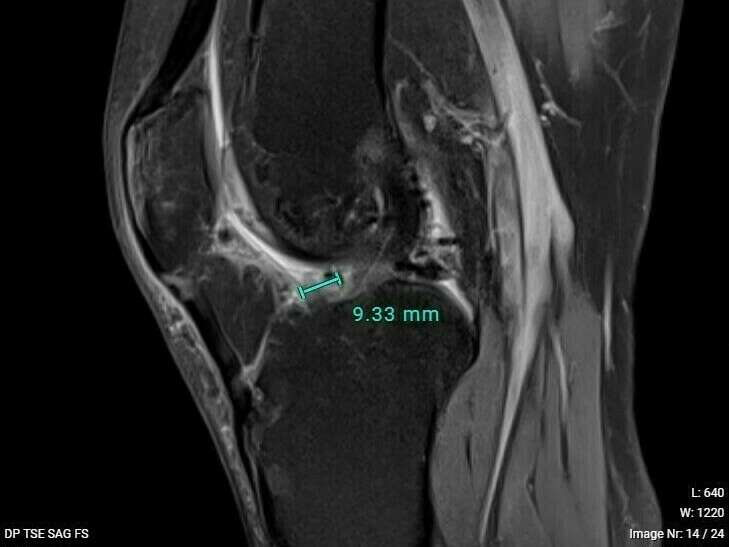

Le diagnostic de cette lésion se fait par la recherche de signes cliniques évocateurs et par l’IRM qui retrouve généralement un nodule à la face antérieure de la plastie ligamentaire au niveau de l’échancrure inter-condylienne sur lequel vient buter la trochlée fémorale.